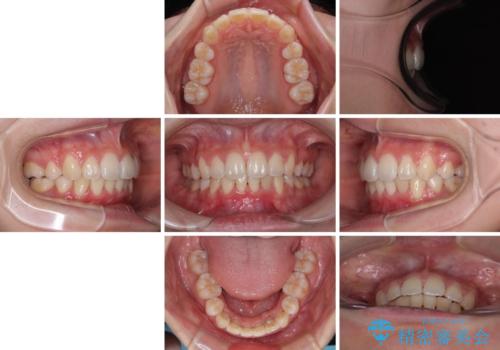

飛び出した上顎前歯 ワイヤー装置にて抜歯矯正治療

- 前に傾斜して飛び出した上顎前歯を気にして来院された患者様です。

上下前歯の前後差が大きく、下顎前歯が隠れるほど深い咬合で、咬合力が強い状態でした。

口元の突出感を改善するために、上下左右の第一小臼歯4本を抜歯し、ワイヤー装置にて矯正治療を行うこととしました。

深い咬み合わせの改善に時間がかかりましたが、下顎前歯がしっかりと見えるまでに整えることができ、口元の突出感も大幅に改善することができました。